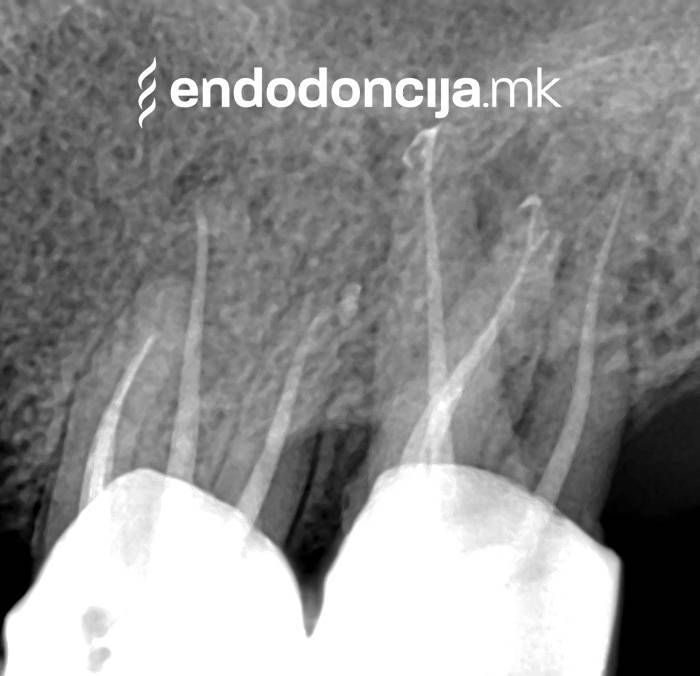

Εκτός από την ανίχνευση των ριζικών καναλιών, η ενδελεχής προετοιμασία και η απολύμανση του ριζικού σωλήνα είναι η προϋπόθεση για μια επιτυχημένη συνολική θεραπεία. Μέσω της χρήσης των νεότερων οργάνων και αντιβακτηριακών διαλυμάτων, όλα τα υπολείμματα ιστών και τα βακτήρια που υπάρχουν μπορούν να εξαλειφθούν.

Κατά τη διάρκεια της επεξεργασίας του ριζικού σωλήνα, τα λεπτά όργανα ενδέχεται να σπάσουν. Αυτό μπορεί να αποτελέσει εμπόδιο για την πλήρη προετοιμασία και τον καθαρισμό του ριζικού σωλήνα. Με μια μικροσκοπική επεξεργασία του ριζικού σωλήνα μπορεί να είναι δυνατή η απομάκρυνσή τους υπό ορισμένες συνθήκες, χωρίς να καταστρέφεται η ουσία των δοντιών.